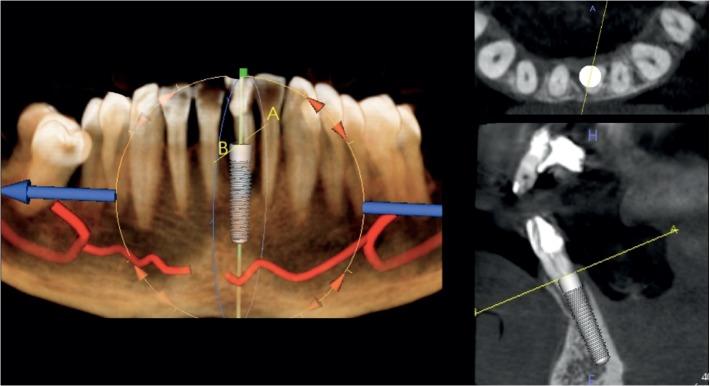

A total of 41 tapered implants were allocated into two groups: the test group ( = 11; 3 males and 8 females; mean age: 62.8 ± 10.7) which received 18 implants as type 1 fresh extraction sockets after teeth removal and the control group ( = 7; 4 males and 3 females; mean age: 65.4 ± 9.7) which received 23 implants placed in healed sockets for a period of at least 3 months. Both the ITV and ISQ data were recorded at the time of insertion ( ). Since ITV (test group) and ITV/ISQ (control group) values were useful for the immediate loading protocol, a screw-retained temporary crown was immediately loaded. ISQ values were recorded after a healing period of 4 months ( ).

总共分配了 41 个锥形种植体,分为两组:实验组(n=11;3 名男性和 8 名女性;平均年龄:62.8±10.7),其中 18 个种植体为拔牙后即刻负载的 1 型新鲜拔牙窝;对照组(n=7;4 名男性和 3 名女性;平均年龄:65.4±9.7),其中 23 个种植体植入愈合时间至少 3 个月的拔牙窝中。在插入时()记录 ITV 和 ISQ 数据。由于 ITV(实验组)和 ITV/ISQ(对照组)值对即刻负载方案有用,因此立即加载螺丝固位临时冠。在愈合期 4 个月后()记录 ISQ 值。